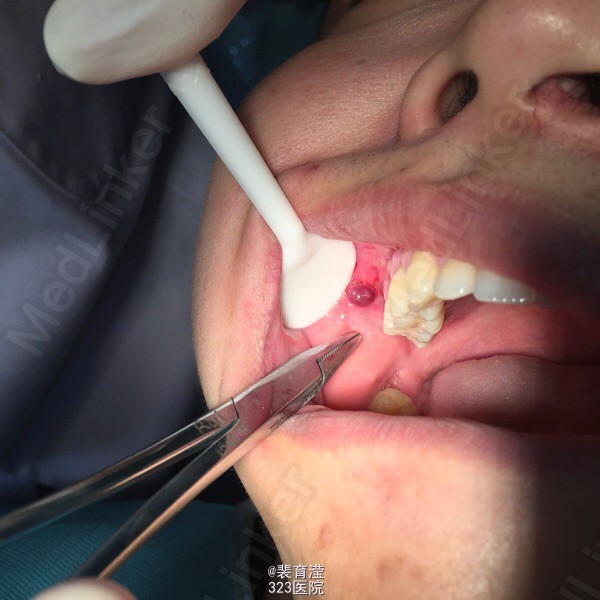

诊断:异物囊肿 右下第三磨牙阻生 处理:1.局麻下切除异物囊肿,缝合,止血。 2.右下第三磨牙局麻下 拔除 搔刮牙槽窝 止血。